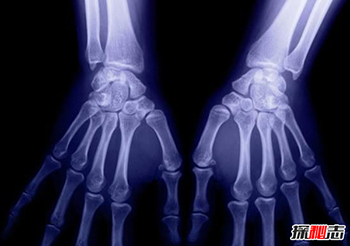

X射线应用于医学诊断,主要依据X射线的穿透作用、差别吸收、感光作用和荧光作用,也就是大家所“拍摄”的X光。

由于X射线穿过人体时,受到不同程度的吸收,如骨骼吸收的X射线量比肌肉吸收的量要多,那么通过人体后的X射线量就不一样,这样便携带了人体各部密度分布的信息,在荧光屏上或摄影胶片上引起的荧光作用或感光作用的强弱就有 较大差别,因而在荧光屏上或摄影胶片上将显示出不同密度的阴影。

根据阴影浓淡的对比,结合临床表现、化验结果和病理诊断,即可判断人体某一部分是否正常。

X射线的用途主要是探测骨骼的病变,但对于探测软组织的病变也相当有 用。